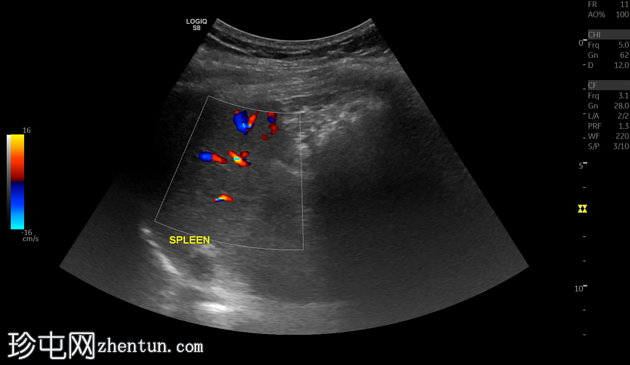

超声

纵切面

脾脏大小正常,纵轴约8.15厘米。脾实质内可见一孤立、边界清晰的高回声灶,符合钙化表现。该钙化灶后方可见声影,未见相关肿块、囊肿或血管异常。无脾周积液或脾肿大。

脾脏钙化通常为良性,且多为偶然发现。